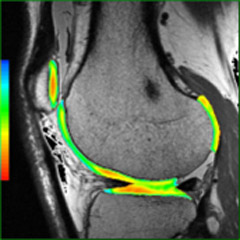

Specialized Magnetic Resonance Imaging (MRI) methods such as diffusion weighted MR (DW-MR), dynamic MR, spectroscopy, and functional methods have evolved to the point where they are able to provide unique measurements of tissue properties. A multi-parametric MR approach generates zones within a lesion that reflect heterogeneity and often display characteristic patterns. These attributes have proven to be useful in the diagnosis of tumors, monitoring tumor growth, and guiding biopsies. Consequently, multi-parametric studies are often used in stroke diagnosis and in the diagnosis of cancer related lesions. While extremely useful, quantifying the information from multi-parametric studies can be very challenging and time consuming. READY View clinical image READY View helps you get the most from multi-parametric exams by enabling analysis of MR data sets with multiple images for each scan location. The platform offers a combination of protocols, applications, and tools that help you make quantified analyses of multiple data sets quickly and easily. Highlights Guided workflows to help analyze MR data. Customizable workflows and application with adjustable layouts, personalized parameter settings, custom review steps. Accessible from PC, laptop, PACS/RIS workstation for streamlined workflow. Provides additional clinical information through time curves and color parametric images. Provides protocols for multi-parametric data processing. Enables fusion of color parametric images with anatomical 2D or 3D images with simple “drag and drop” method. Enables MR to MR image registration to reduce patient motion effects.